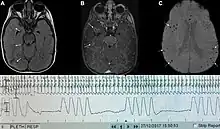

| Graph showing Biot's respiration and other pathological breathing patterns. | |

Biot's breathing or ataxic breathing, is an abnormal pattern of breathing characterized by variable tidal volume, random apneas, and no regularity.[1] It is named for Camille Biot, who characterized it in 1876.[2][3]

Biot's respiration is caused by damage to the medulla oblongata and pons due to trauma, stroke, opioid use, and increased intracranial pressure due to uncal or tentorial herniation.[1][4] Often this condition is also associated with meningitis.[2]

In common medical practice, Biot's respiration is often mistaken for Cheyne–Stokes respiration, part of which may have been caused by them both being described by the same person studying both.[1]